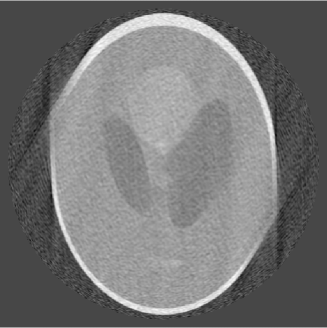

The limited angle problem is well known to be ill-posed. Below we present our reconstruction with noise data. We use again the Shepp-Logan head phantom but add noise in the data, which is Gaussian normally distributed with zero mean and a standard deviation 0.03. The noise is about 2% in the data. For limited angle, we choose and , respectively, which correspond to data limited over an arc of and , respectively. The reconstructed images by our algorithm with and are given in Figure 5.

These reconstruction should be compared with the left image in Figure 3 and the image in Figure 4, respectively, which are the reconstructed images based on the same limited angle data but without noise. These images indicate that our method is relatively stable, in the sense that the reconstructed images are not distorted much by the noise.